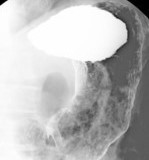

Gastroduodenoscopy

バリウム検査で異常を指摘された方

健診(検診)の結果で、胃炎や胃ポリープなどの指摘を受けた方は、精密検査として胃内視鏡検査を行います。